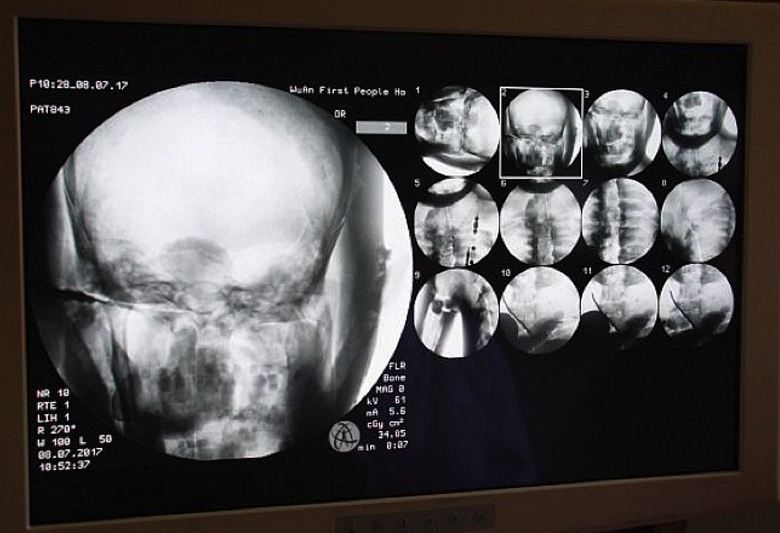

Tutkijat suostuivat mielellään, koska he olivat itse kiinnostuneita tämä mielenkiintoinen tutkimus. Ja tämän vuoden 8. heinäkuuta aivan temppelissä Dinghuille tehtiin muinaisen buddhalaisen muumion tomografia munkki. Lääkärit toivat tänne tarvittavat välineet ja viettivät skannaa muumion sisäinen sisältö. Olimme järkyttyneitä yksinomaan kaikki, ts. tutkijoiden, mutta myös munkkien, pyhiinvaeltajat, jotka kokoontuivat tähän ennennäkemättömään luostariin tapahtuma, tietysti, ja tiedotusvälineiden työntekijät. Kävi ilmi, että nivelet, Tuhatvuotiaan munkan Tsa Xianin luut ja hampaat ovat kuin elävien luut ja hampaat henkilö. Lisäksi hänen aivonsa säilyivät täydellisesti.

Se on vain uskomatonta, tohtori Wu kommentoi. Yongqing (Wu Yongqing), joka suoritti suoraan tomografian muumioita. En voi edes uskoa kuinka ihmisen pääosat ovat Yli tuhat vuotta sitten balzamoitu, säilytetty “terve” tila, jopa aivot! Mutta munkit itse eivät ole näkemättä mitään yliluonnollista tässä, he ovat varmoja, että mestari Tsy Xian ei kuollut ollenkaan, hän yksinkertaisesti astui samadhin tilaan, alkaen joka jonain päivänä herää varmasti. Loppujen lopuksi muumion skannaaminen osoitti: hänen ruumiinsa on valmis uuteen elämään …